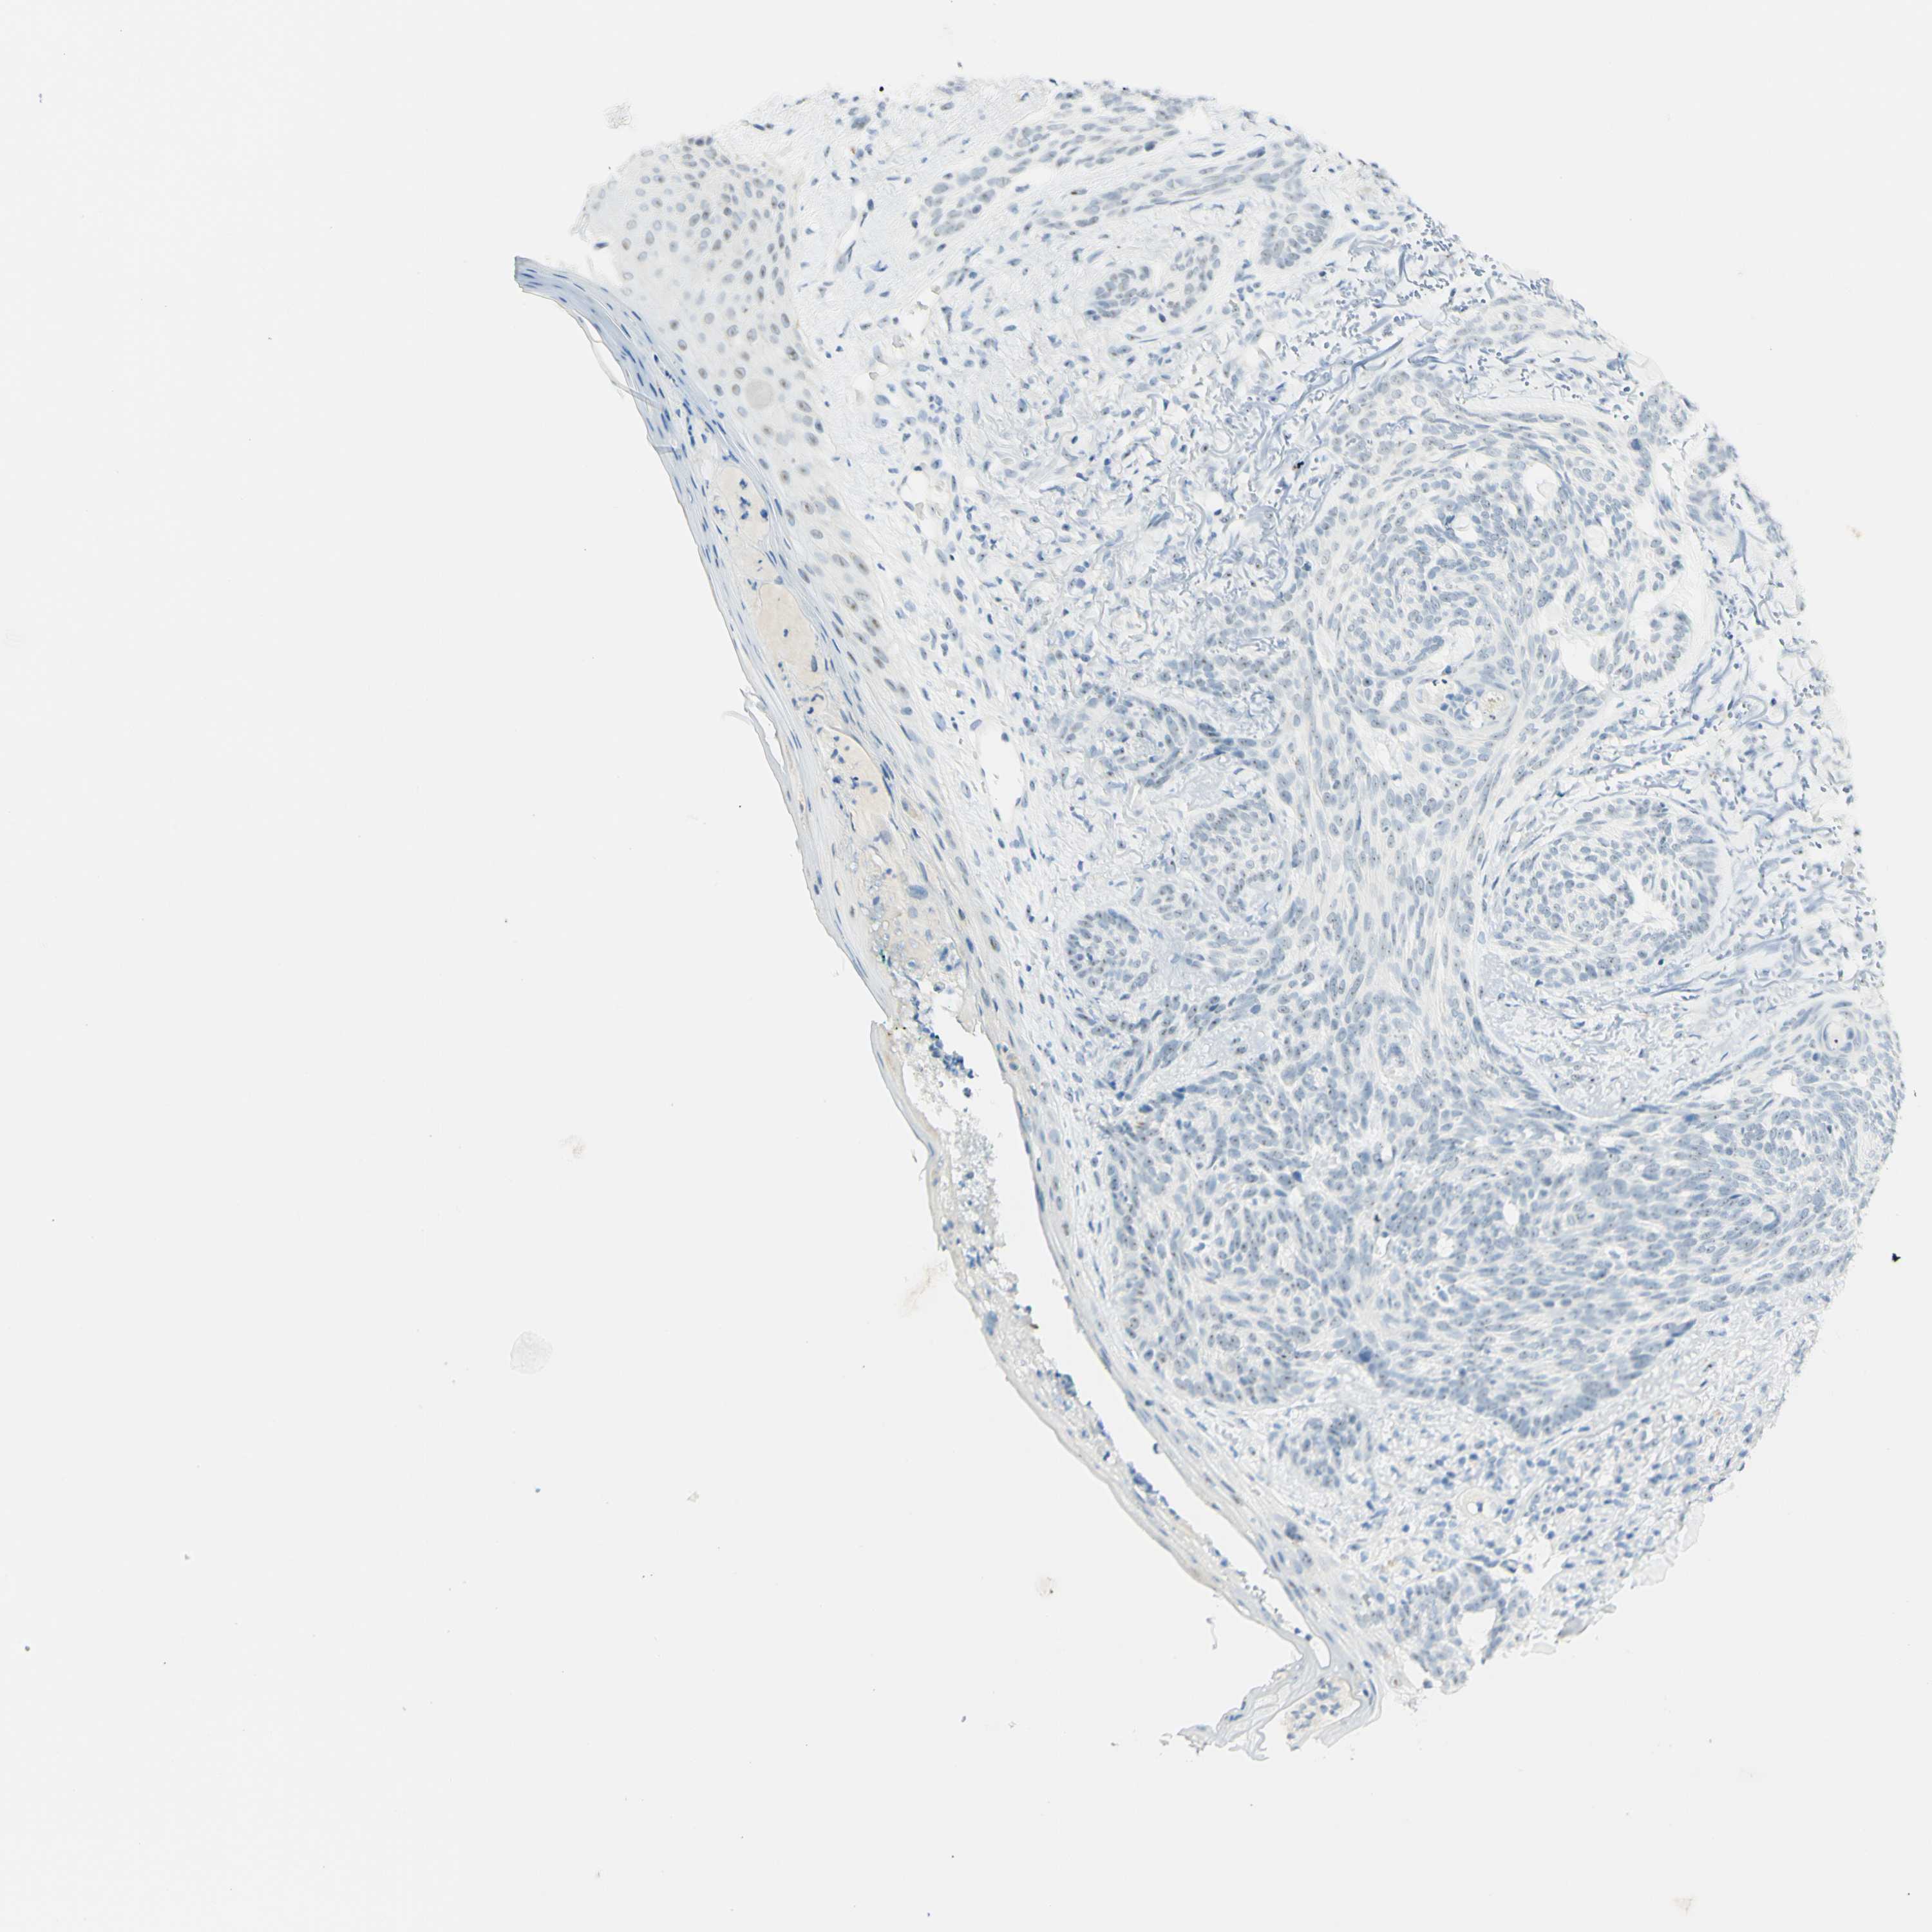

SKIN CANCER - Protein expressioni

A mouse-over function shows sample information and annotation data. Click on an image to view it in a full screen mode. Samples can be filtered based on level of antibody staining by selecting one or several of the following categories: high, medium, low and not detected. The assay and annotation is described here.

Antibody stainingi

Antibody staining in the annotated cell types in the current human tissue is reported as not detected, low, medium, or high, based on conventional immunohistochemistry profiling in selected tissues. This score is based on the combination of the staining intensity and fraction of stained cells.

Each image is clickable and will lead to virtual microscopy that enables deeper exploration of all samples and also displays staining intensity scores, fraction scores and subcellular localization as well as patient and tissue information for each sample.

Antibody CAB026403

Basal cell carcinoma

Squamous cell carcinoma, NOS

Squamous cell carcinoma, metastatic, NOS